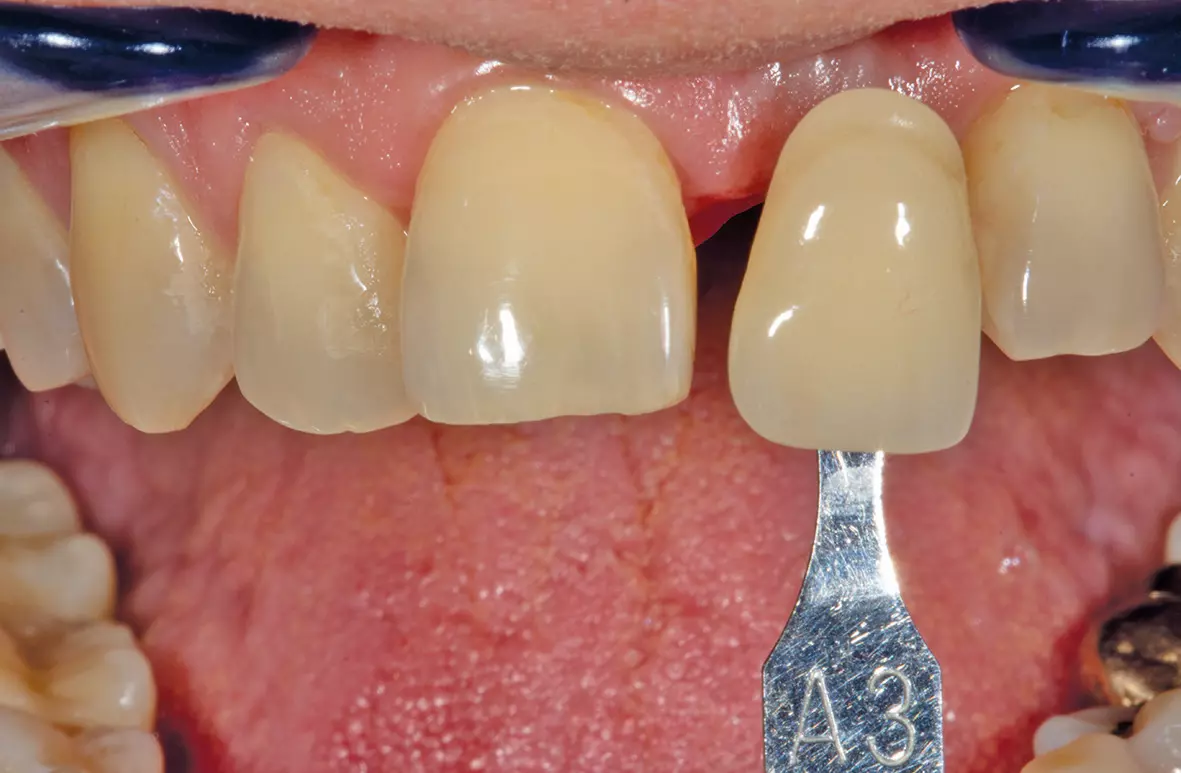

Nun konnte die Reaktion der Gingiva abgewartet, eine genaue Zahnfarbkontrolle erfolgen sowie eventuelle Formkorrekturen analysiert und in die definitive Versorgung übernommen werden. Für die Umsetzung wurde das Modell eingescannt. Digital wurde jetzt die endgültige Krone konstruiert. Dabei kam das Ceramill CAD/CAM-System von Amann Girrbach GmbH zum Einsatz. Im Ceramill Map Scanner wurden die erforderlichen Modelle eingescannt bzw. digitalisiert (Abb. 19). Da die Zahnform schon vorgegeben war, konnte man über einen Situationsscan die spätere Form im Scan erfassen und musste danach lediglich die zu verblendende Fläche reduzieren. In der Ceramill Mind Konstruktionssoftware wurden alle weiteren Schritte in der Folge abgearbeitet und die Krone schließlich in der Ceramill Motion Fräs- und Schleifeinheit aus Zirkon (Ceramill ZI) gefräst. Wichtig war hierbei, dass der Schraubenkanal in Zirkon gefasst blieb (Abb. 20 und 21).

Hierdurch war beim Einschrauben der Implantatkrone eine gute Führung vorhanden und die Verblen dung konnte nicht versehentlich durch den Schraubendreher beschädigt werden. Für die genaue Farbwahl wurden die Zähne mit einem PolarEyes-Filter fotografiert, um die genauen Strukturen des Zahnes und seiner einzelnen Schichten zu analysieren und später in Keramik umzusetzen (Abb. 22-24).